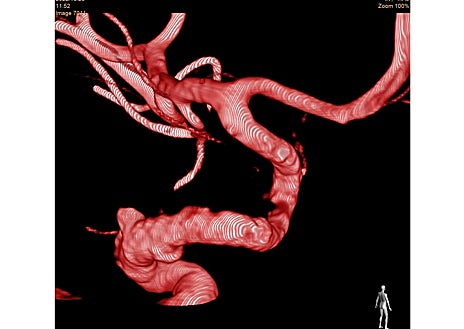

Se trata del angiógrafo biplano de Philips Azurion 7 B20/15, equipo que incorpora dos tubos de rayos X con detectores de 20» y de 15». «La tecnología del equipo nos permite realizar tratamientos mínimamente invasivos de la forma más eficaz y segura, ya que se utiliza monitorización en tiempo real de la anatomía cerebral en dos planos del espacio simultáneos, y además de forma tridimensional (3D) y cuatridimensional (4D)», señala el doctor Aurelio Vega.

Además, indica el doctor Méndez, incorpora técnicas avanzadas de seguimiento de cateterismos por fluoroscopia para navegación endovascular, software de reconstrucción 3D y 4D de la anatomía y patología vascular cerebral, capacidad de fusionar las imágenes angiográficas con TAC y Resonancia Magnética en tiempo real, y realizar TAC cerebral y TAC perfusión de forma ultrarrápida durante los procedimientos.